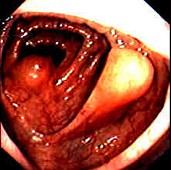

问题 女性,60岁,无临床症状,查体无明显异常,体检时的结肠镜检查图片(图1、2),2年后复查肠镜图片(图3、4),此患者最可能的诊断是 ( )

选项 A.Crhon病 B.大肠癌 C.脂肪瘤 D.大肠息肉 E.溃疡性结肠炎

答案 C